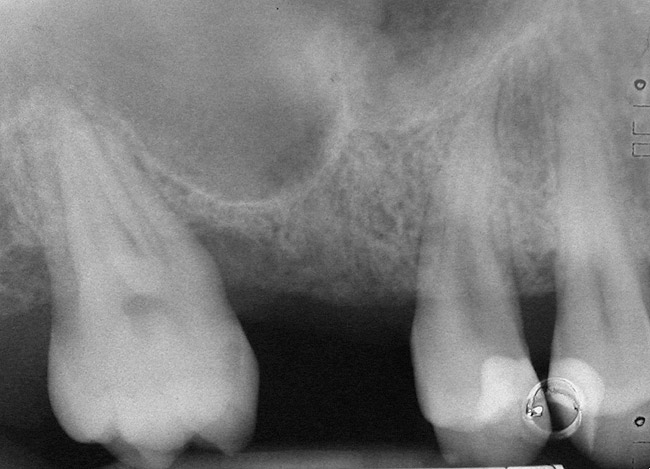

A 53-year-old female was referred for evaluation of a fracture of tooth No. 24. The tooth had been treated endodontically 5 years prior. The radiograph revealed a complete fracture of the tooth involving the crown (Figure 12). Tooth extraction and immediate placement of a an implant that was 10 mm in length and 3.75 in diameter was planned.

At the time of surgery, the tooth was extracted without harvesting any mucosal flap because the implant site was prepared by means of a pilot drill bur (Figure 13) and alternating osteotomes (Figure 14A and Figure 14B). The implant was positioned and showed primary stability. The implant was loaded 2 days after surgery. Then, splinted PFM crowns supported by custom gold abutments were delivered. At 6 months posttreatment, the radiograph revealed no bone resorption and the clinical result was optimal (Figure 15A and Figure 15B).

Figure 12  Preoperative radiograph shows fractured tooth No. 24.

Figure 12